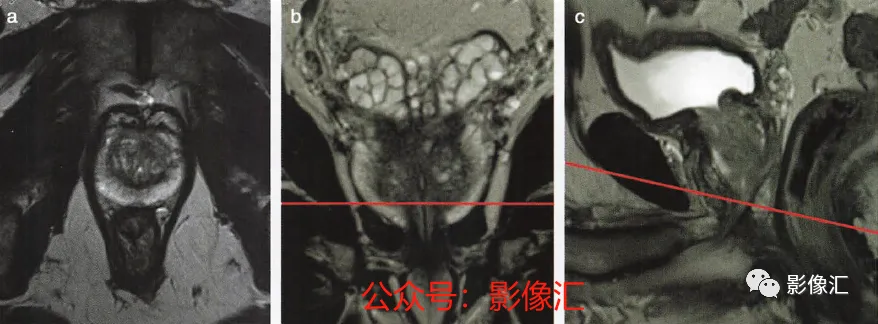

7. 前列腺下部水平的横轴面(图2.25)